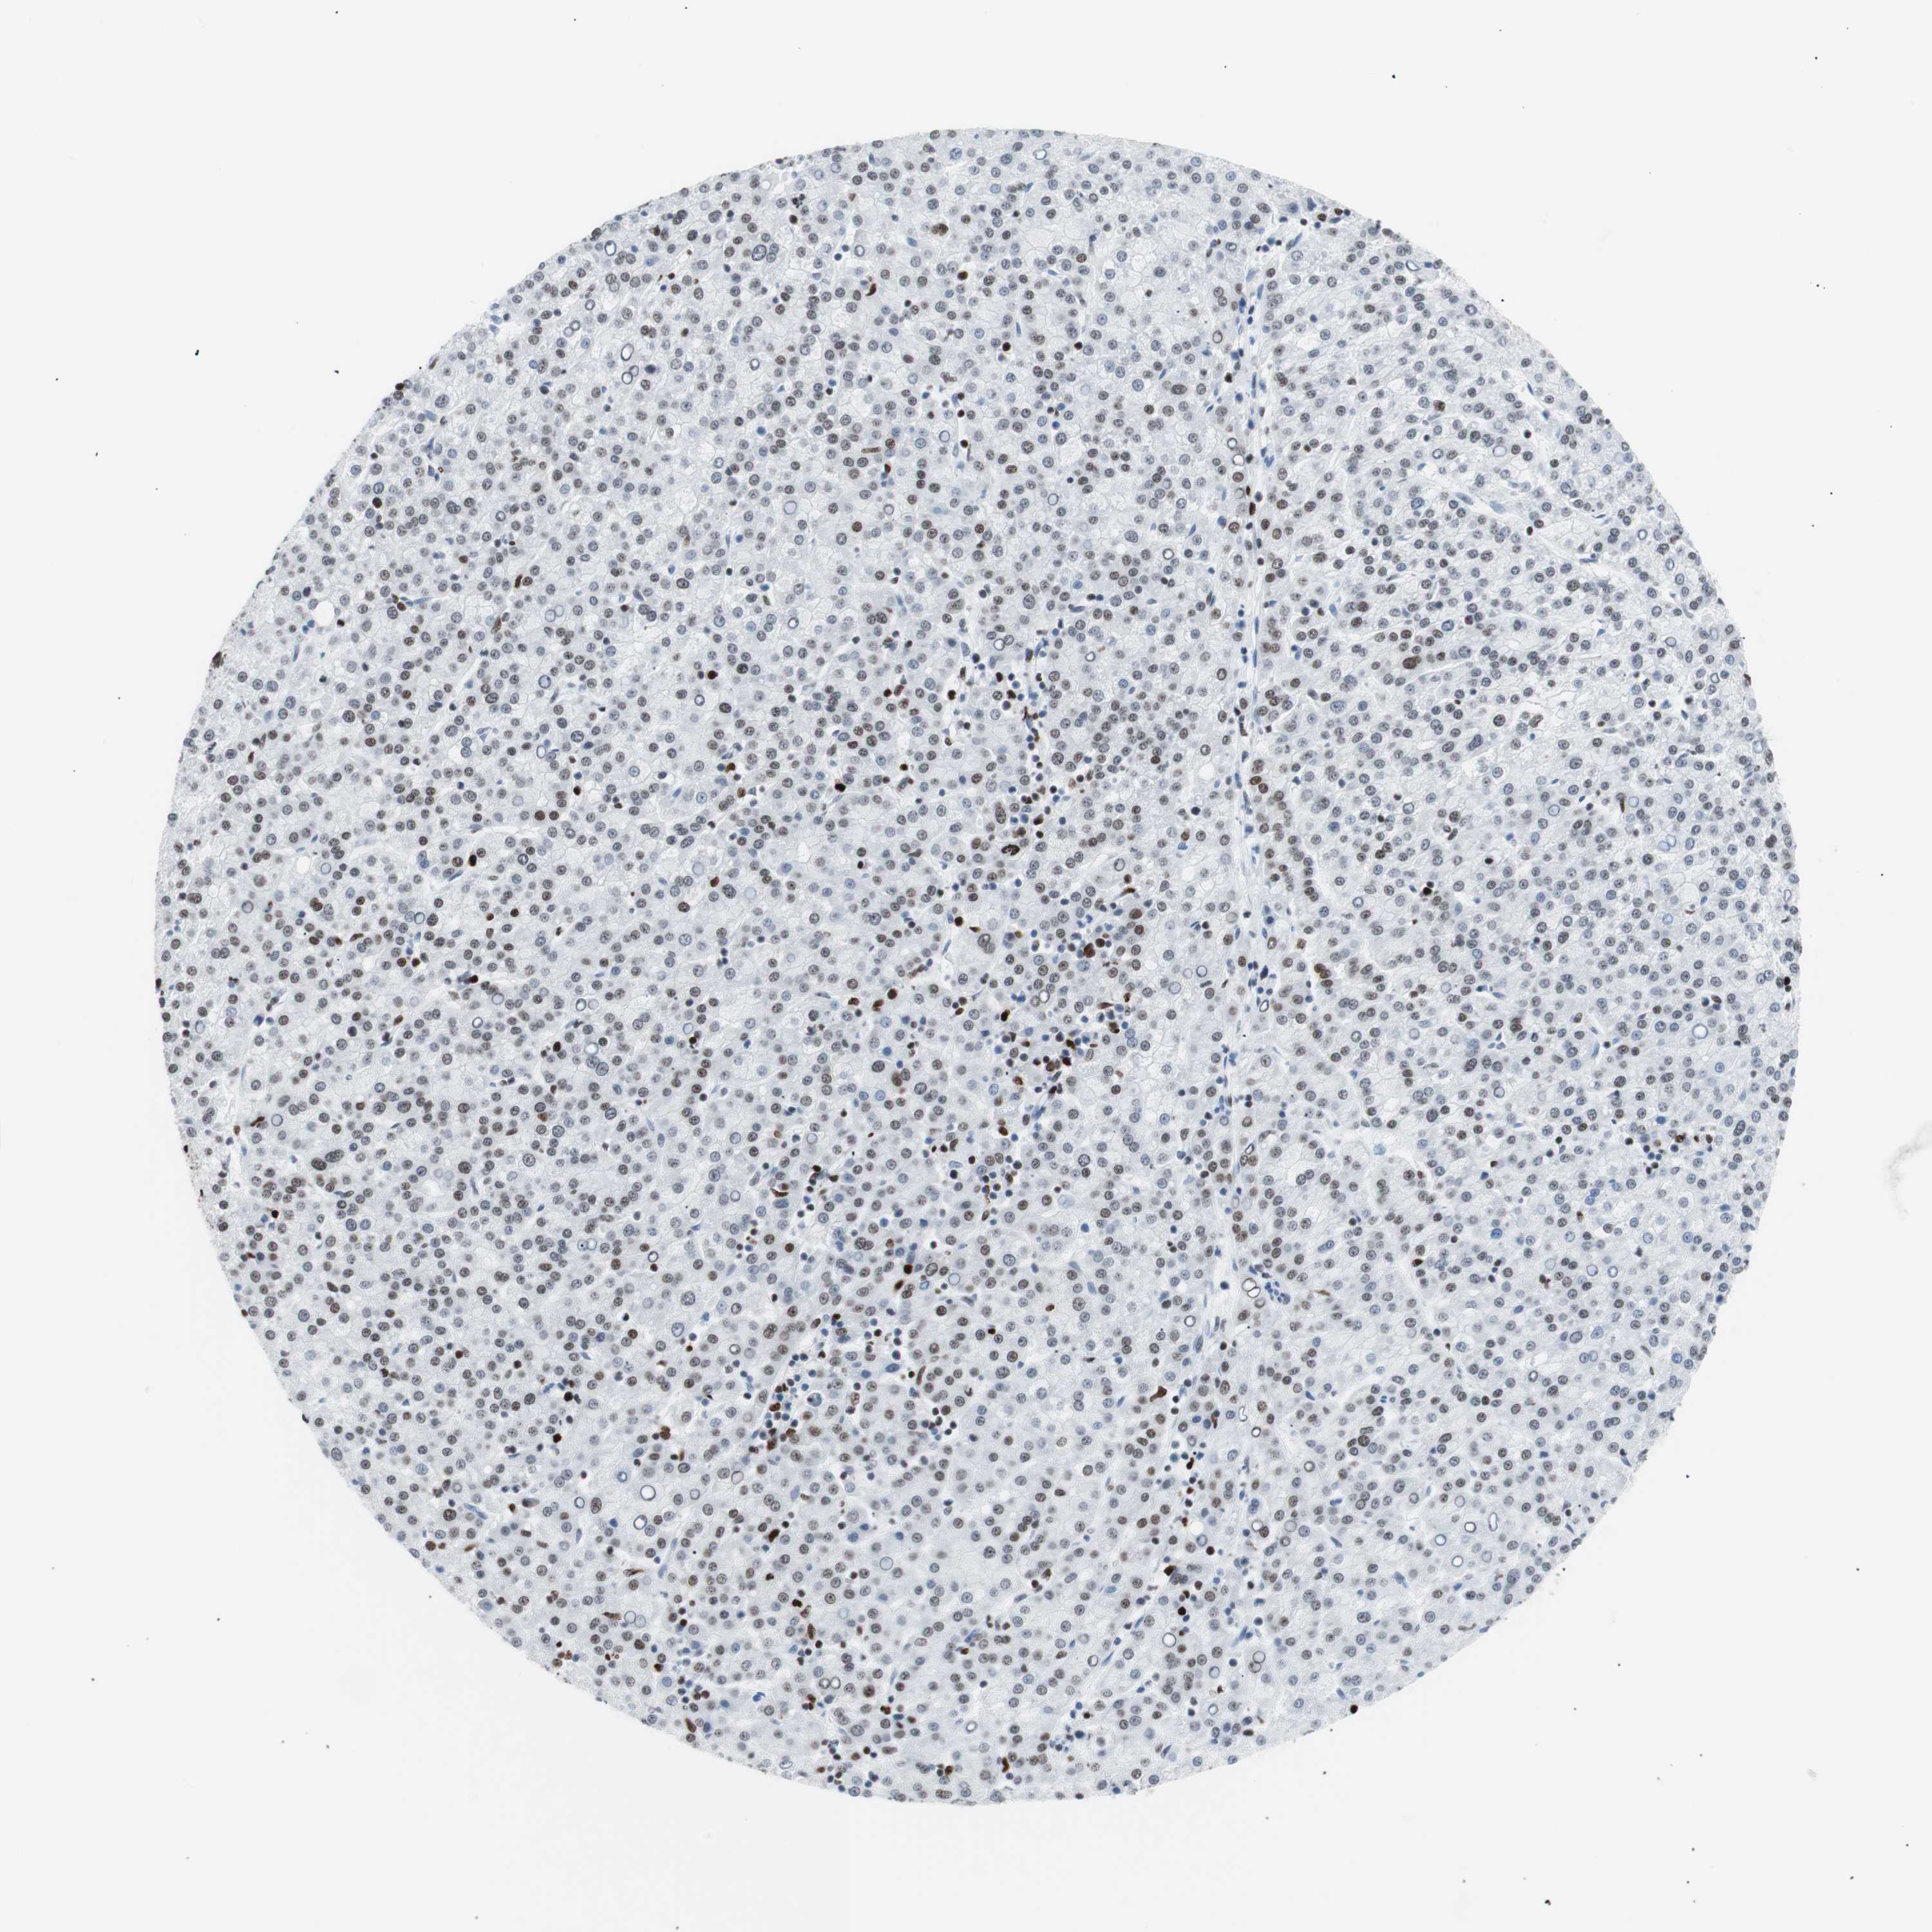

LIVER CANCER - Protein expressioni

A mouse-over function shows sample information and annotation data. Click on an image to view it in a full screen mode. Samples can be filtered based on level of antibody staining by selecting one or several of the following categories: high, medium, low and not detected. The assay and annotation is described here.

Note that samples used for immunohistochemistry by the Human Protein Atlas do not correspond to samples in the TCGA dataset.

Antibody stainingi

Antibody staining in the annotated cell types in the current human tissue is reported as not detected, low, medium, or high, based on conventional immunohistochemistry profiling in selected tissues. This score is based on the combination of the staining intensity and fraction of stained cells.

Each image is clickable and will lead to virtual microscopy that enables deeper exploration of all samples and also displays staining intensity scores, fraction scores and subcellular localization as well as patient and tissue information for each sample.

Antibody CAB004213

Staining

High

Medium

Low

Not detected

Intensity

Strong

Moderate

Weak

Negative

Quantity

>75%

75%-25%

<25%

None

Location

Nuclear

Cytoplasmic/membranous

Cytoplasmic/membranous,nuclear

Cholangiocarcinoma

Carcinoma, Hepatocellular, NOS